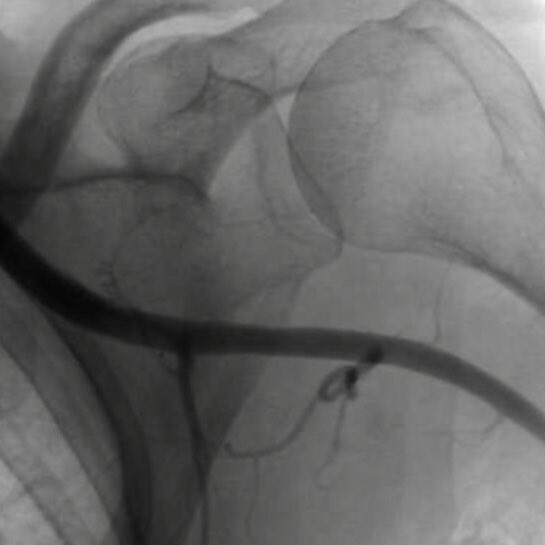

Then went #PercAx for heavily calcified LM in cardiogenic shock after we were unable to get catheters up from right and left radial, right femoral…and finding this gem in the left iliac

RajTayalMD's tweet image. Then went #PercAx for heavily calcified LM in cardiogenic shock after we were unable to get catheters up from right and left radial, right femoral…and finding this gem in the left iliac